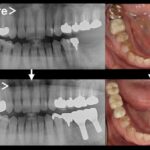

患者様は60代の女性の方です。当院にメンテナンスで通院しておられましたが、他院にて入れた左下の被せ物が虫歯で取れてしまいました。虫歯をしっかり削っていくと、ご自身の歯がほとんどなくなってしまい、被せ物を再度行うことが不可能となり、残念ながら抜歯となりました。

抜歯後のお口の状態がこちらになります。

こちらがノンクラスプデンチャーの写真になります。

適合が問題ないことや歯茎とぶつかっている部位がないことなど念入りに確認し、噛み合わせも細かく調整を行いセットいたしました。毎日ご自身で着脱を行なってもらいますので、着脱の練習も十分にしてもらいました。

こちらの写真を見て、入れ歯をしているなと気がつく一般の人はかなり少ないかと思います。